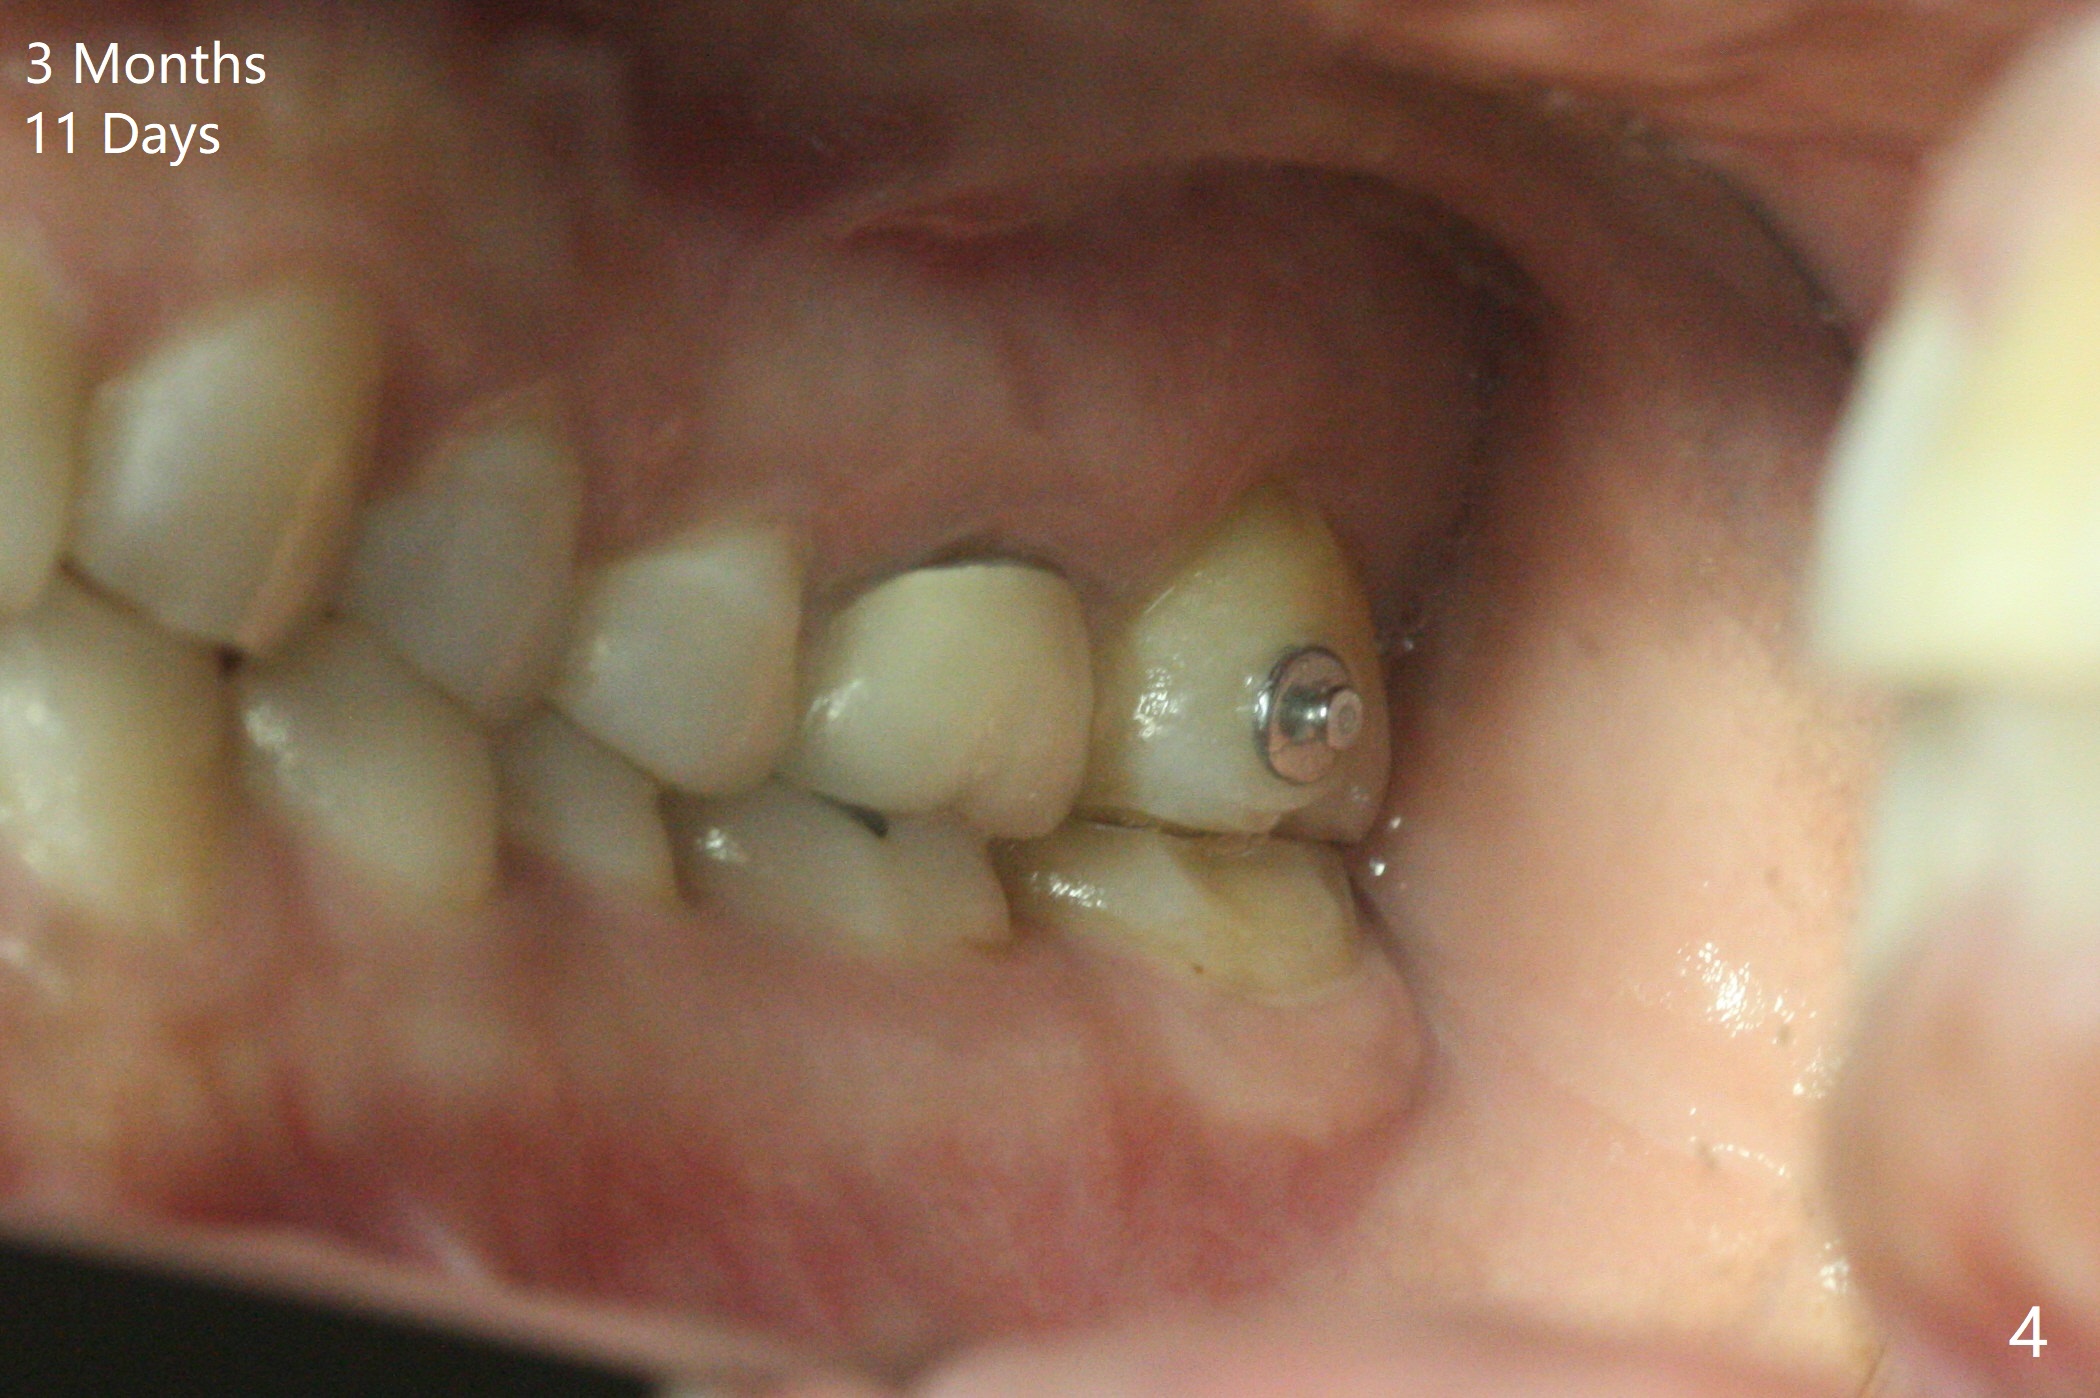

A 51-year-old woman agrees to correct cross bite of R7s 10 years post UR6 crown (Fig.1,2). Composite is placed in LR6 (Fig.3 C) and LL7 for clearance. Lingual buttons are placed in the buccal surface of UR7 (Fig.3 <) and lingual surface of LR7 (Fig.6 ^) with 6 oz. elastic in between. Cross bite correction finishes in 3 months. Photos (Fig.4-6) and PAs (Fig.7,8) are taken 11 days post orthodontic treatment.